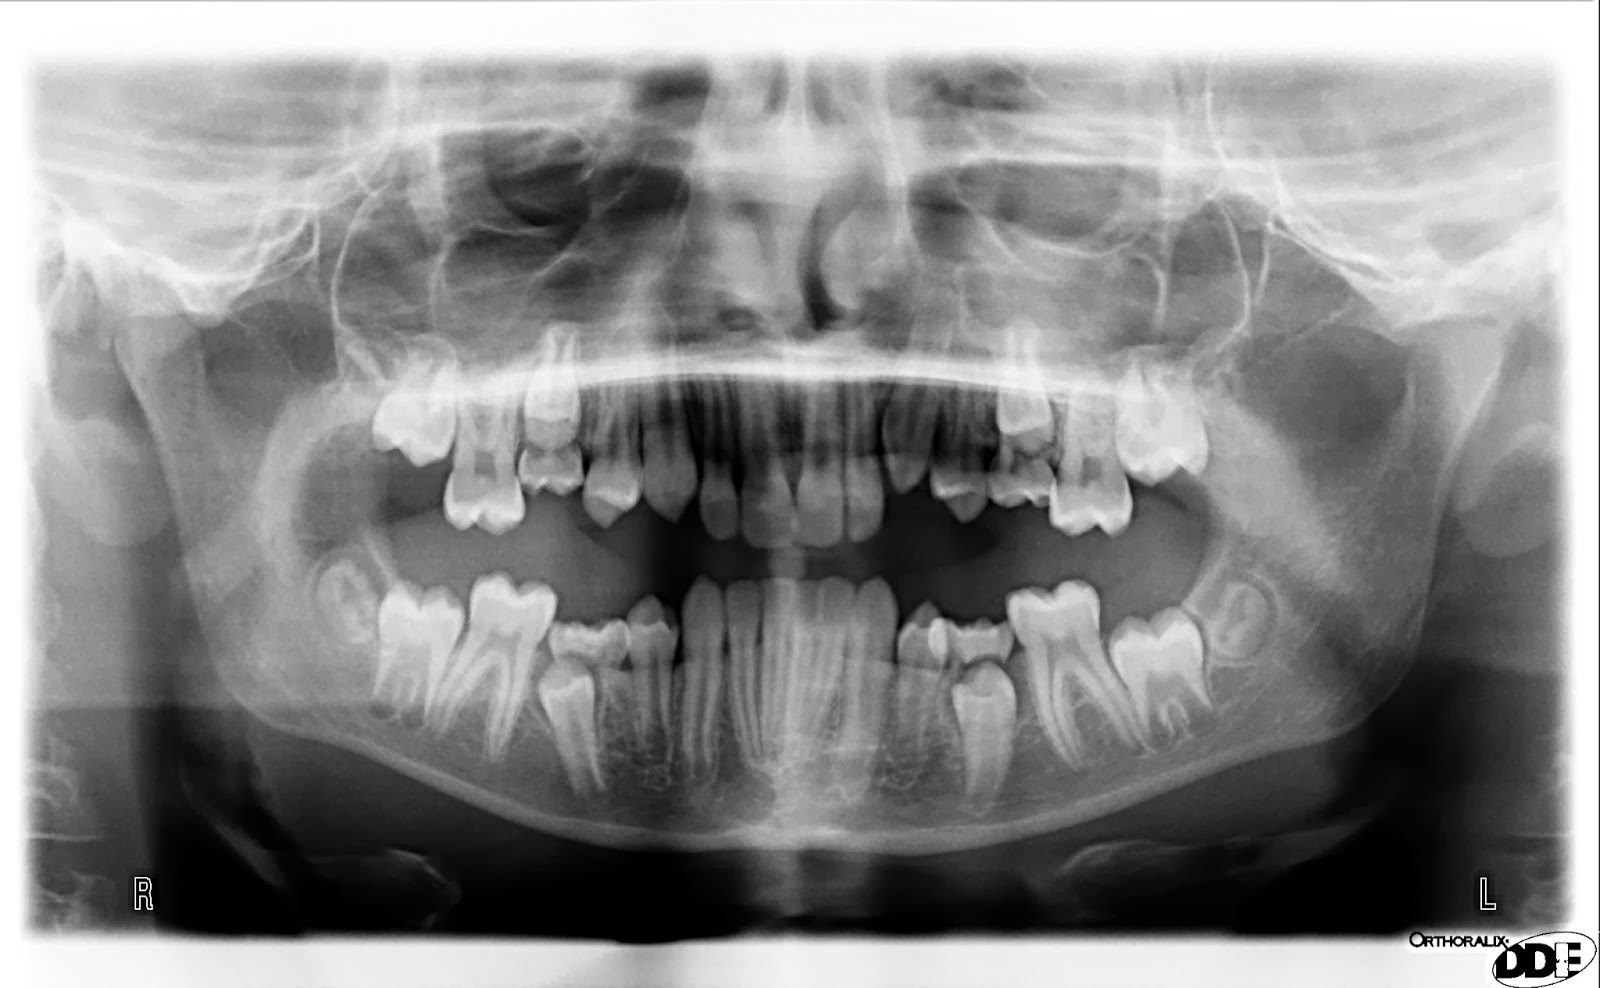

From shutterstock.com

Panoramic XRay Of Crowding Teeth Stock Photo 204889417 Shutterstock Crowded Teeth X Ray The primary causes of teeth crowding include teeth larger than the jaw or a jaw that is too small. malocclusion of teeth is typically diagnosed through routine dental exams. in dental crowding therapy, it is important to quantify the lack of space in the dental arch in order to choose an appropriate orthodontic. Your dentist will examine your. Crowded Teeth X Ray.

Crowded Teeth X Ray . malocclusion of teeth is typically diagnosed through routine dental exams. dental crowding, also referred as swarming, can be characterised as an. in dental crowding therapy, it is important to quantify the lack of space in the dental arch in order to choose an appropriate orthodontic. The primary causes of teeth crowding include teeth larger than the jaw or a jaw that is too small. crowded teeth can be prevented or corrected using braces if crowding is mild (less than 4 mm). Losing baby teeth too early can. Your dentist will examine your teeth and may perform dental x.

Your dentist will examine your teeth and may perform dental x. crowded teeth can be prevented or corrected using braces if crowding is mild (less than 4 mm). dental crowding, also referred as swarming, can be characterised as an. Losing baby teeth too early can. The primary causes of teeth crowding include teeth larger than the jaw or a jaw that is too small. in dental crowding therapy, it is important to quantify the lack of space in the dental arch in order to choose an appropriate orthodontic. malocclusion of teeth is typically diagnosed through routine dental exams.